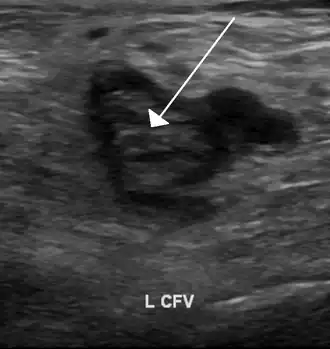

Тромб в левой бедренной вене на УЗИ